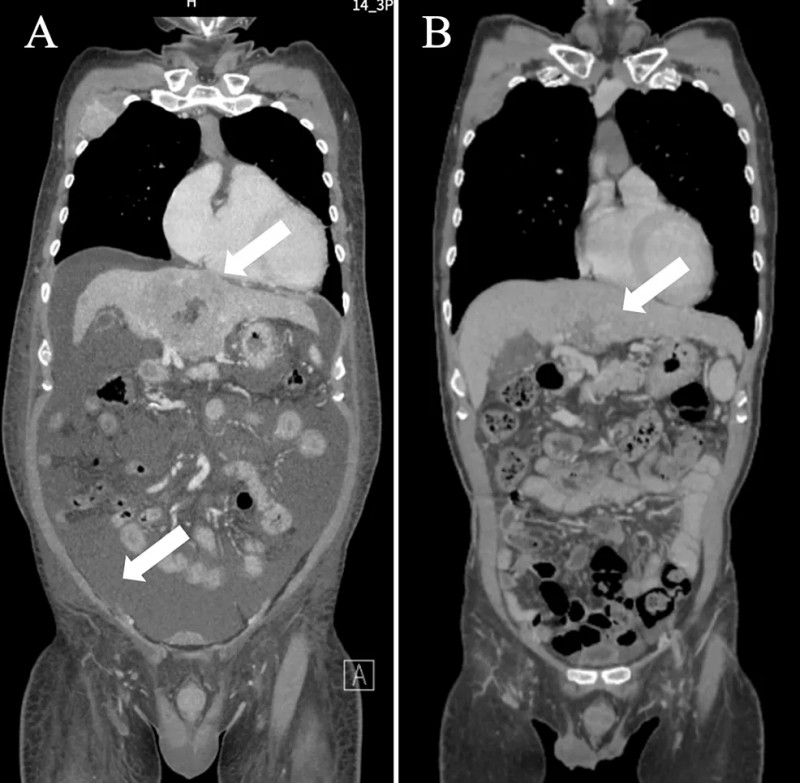

该患者是一位61岁男性,既往有丙型肝炎病毒感染史,因腹胀就诊,后因腹水蓄积超3升紧急入院,最终确诊为ⅣB期(T4N1M1)肝细胞癌(HCC),伴多发淋巴结、肺及骨转移(详见下图1A、2A)。实验室检查提示患者淋巴细胞比例偏低、肝功能受损、肿瘤标志物水平升高,且肝储备功能差(Child-PughC级),药物治疗难度极高,初始给予姑息治疗。

▼患者入院时的初始冠状面CT扫描

▲图源“Cureus”,版权归原作者所有,如无意中侵犯了知识产权,请联系我们删除

治疗后患者病情显著改善:前3个疗程结束,体能状态明显提升,腹胀症状有效缓解;第6个疗程结束后转至原医院复查,Child-Pugh分级已升至A级,CT扫描提示原发肿瘤及转移灶均缩小、腹水完全消失,符合实体瘤疗效评价标准(RECIST)1.1版的部分缓解(详见下图1B、2B);肿瘤标志物显著下降(维生素K缺乏诱导蛋白II恢复正常),白细胞总数及淋巴细胞比例亦恢复至正常水平。鉴于肝储备功能已显著改善,患者在完成第7个免疫联合治疗疗程后,顺利过渡至阿替利珠单抗联合贝伐珠单抗标准化疗。